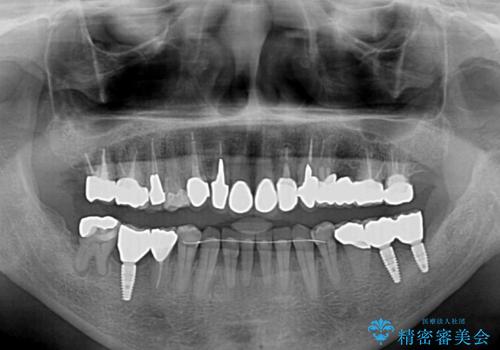

奥歯1歯分を動かすには時間がかかるため、矯正治療には思いの外時間がかかりました。

痛みのある奥歯は必要に応じて根管治療を行い、左下インプラントは角化歯肉の移植により清掃性を向上させ、気になっていた部分をしっかりと改善させることができました。